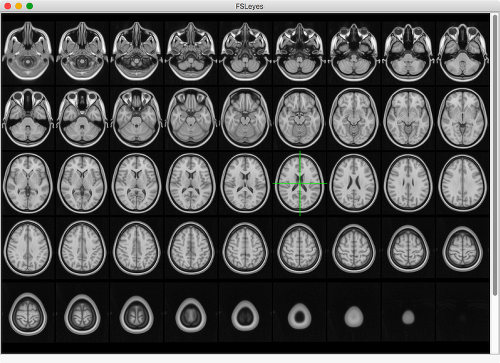

MELODIC mode

This layout is designed to assist in manual classification of ICA components. It provides functionality similar to that of the Melview tool, comprising a lightbox view and plot panels which display the time course and power spectrum of the currently selected component. A classification panel allows you to load, save, and edit the classification labels for each component. See the page on IC classification for more information.